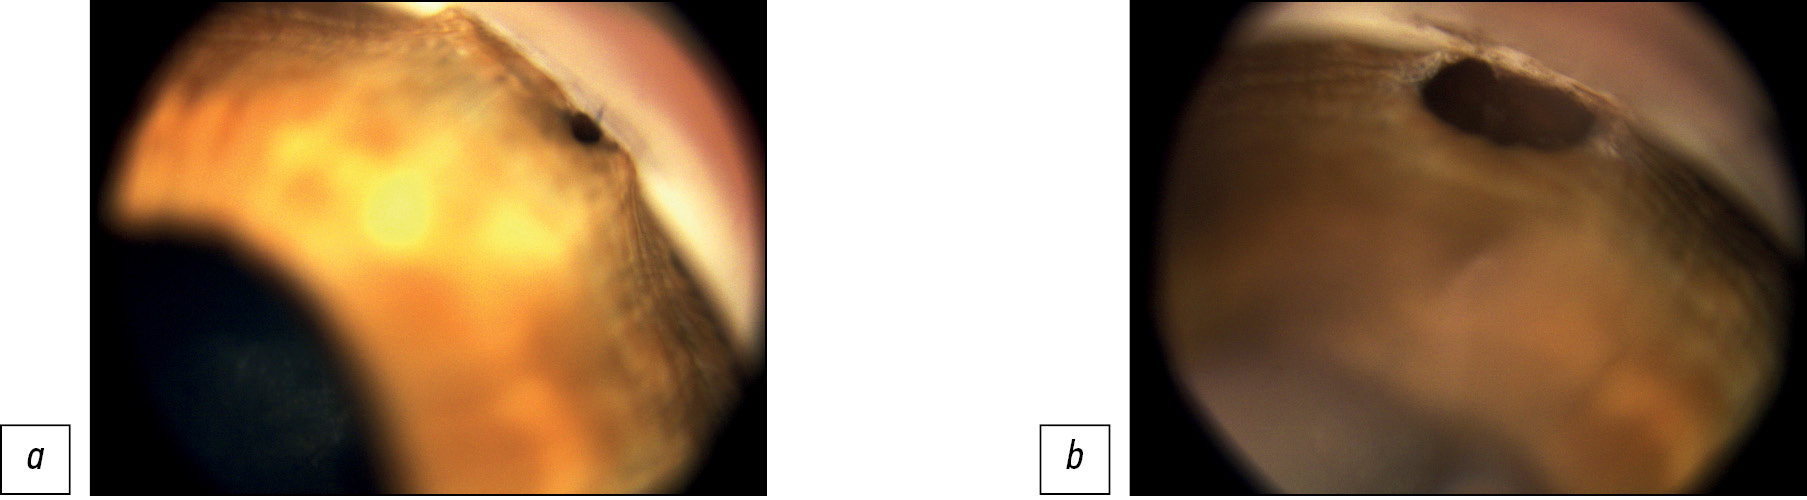

После ТЭ нередко у детей наблюдали врастание краев послеоперационной колобомы радужки в зону ВФ — по краям её (рис. 6), реже – почти полное заращение послеоперационной колобомы радужки и зоны внутренней фистулы (рис. 7).

Рис. 6. Врастание краев послеоперационной колобомы радужки в зону внутренней фистулы.

Рис. 7. Иридотрабекулярное сращение в зоне внутренней фистулы (полный блок с заращением послеоперационной колобомы радужки): а — до лазерной операции; b — после лазерной операции внутренней фистулы и колобома радужки свободны от сращений.

В большинстве случаев лазерной рефистулизации (97,3%) удалось устранить блок ВФ (рис.7 а, b). Из них полный реконструктивный эффект, а именно отсутствие сращений в зоне ВФ, зияние её, получен в 72,6% случаев.